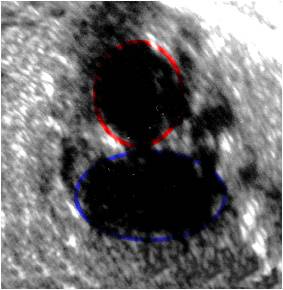

Ecografía fetal que muestra una anomalía cardiaca grave, con un ventrículo único (circulo rojo) y ambos atrios con una extensa comunicación (circulo azul).